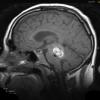

VASCULAR

Cavernous Angioma (9)